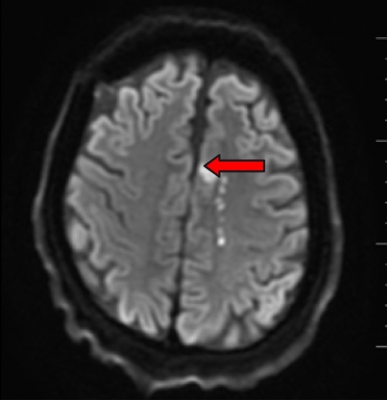

Kontrolní doporučené koagulační odběry nevykazovaly patologii. Následné CT a MR (obr. 3, 4) prokazovaly pouze drobné postischemické změny v povodí ACA vlevo. Primární kardiologické došetření pro suspektní embolizační etiologii neprokázalo zjevnou patologii. Nicméně pacient bude ještě superkonziliárně přešetřen.